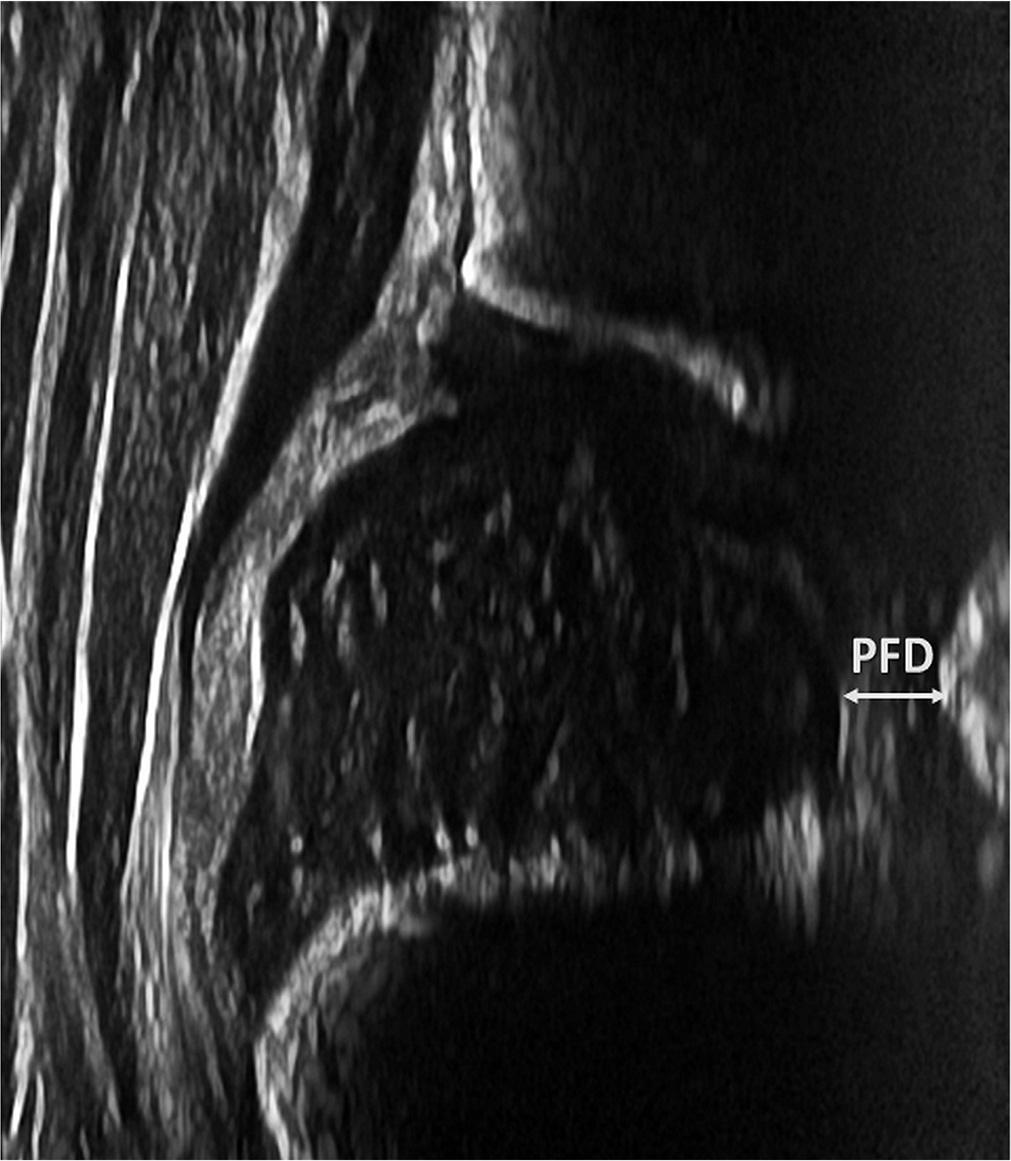

Fig. 3.